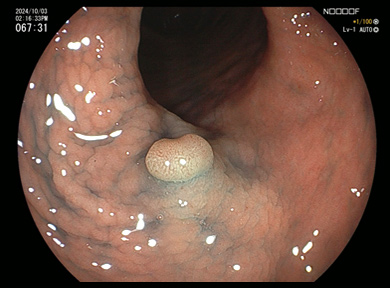

内視鏡検査の所見例

大腸ポリープ

ポリープ切除術

1

IS型といわれる大腸ポリープです。

2

スネアをポリープに引っ掛けます。

3

スネアの輪を絞ります。

4

ポリープを切除、血液のにじみはわずかです。

内視鏡検査の所見例